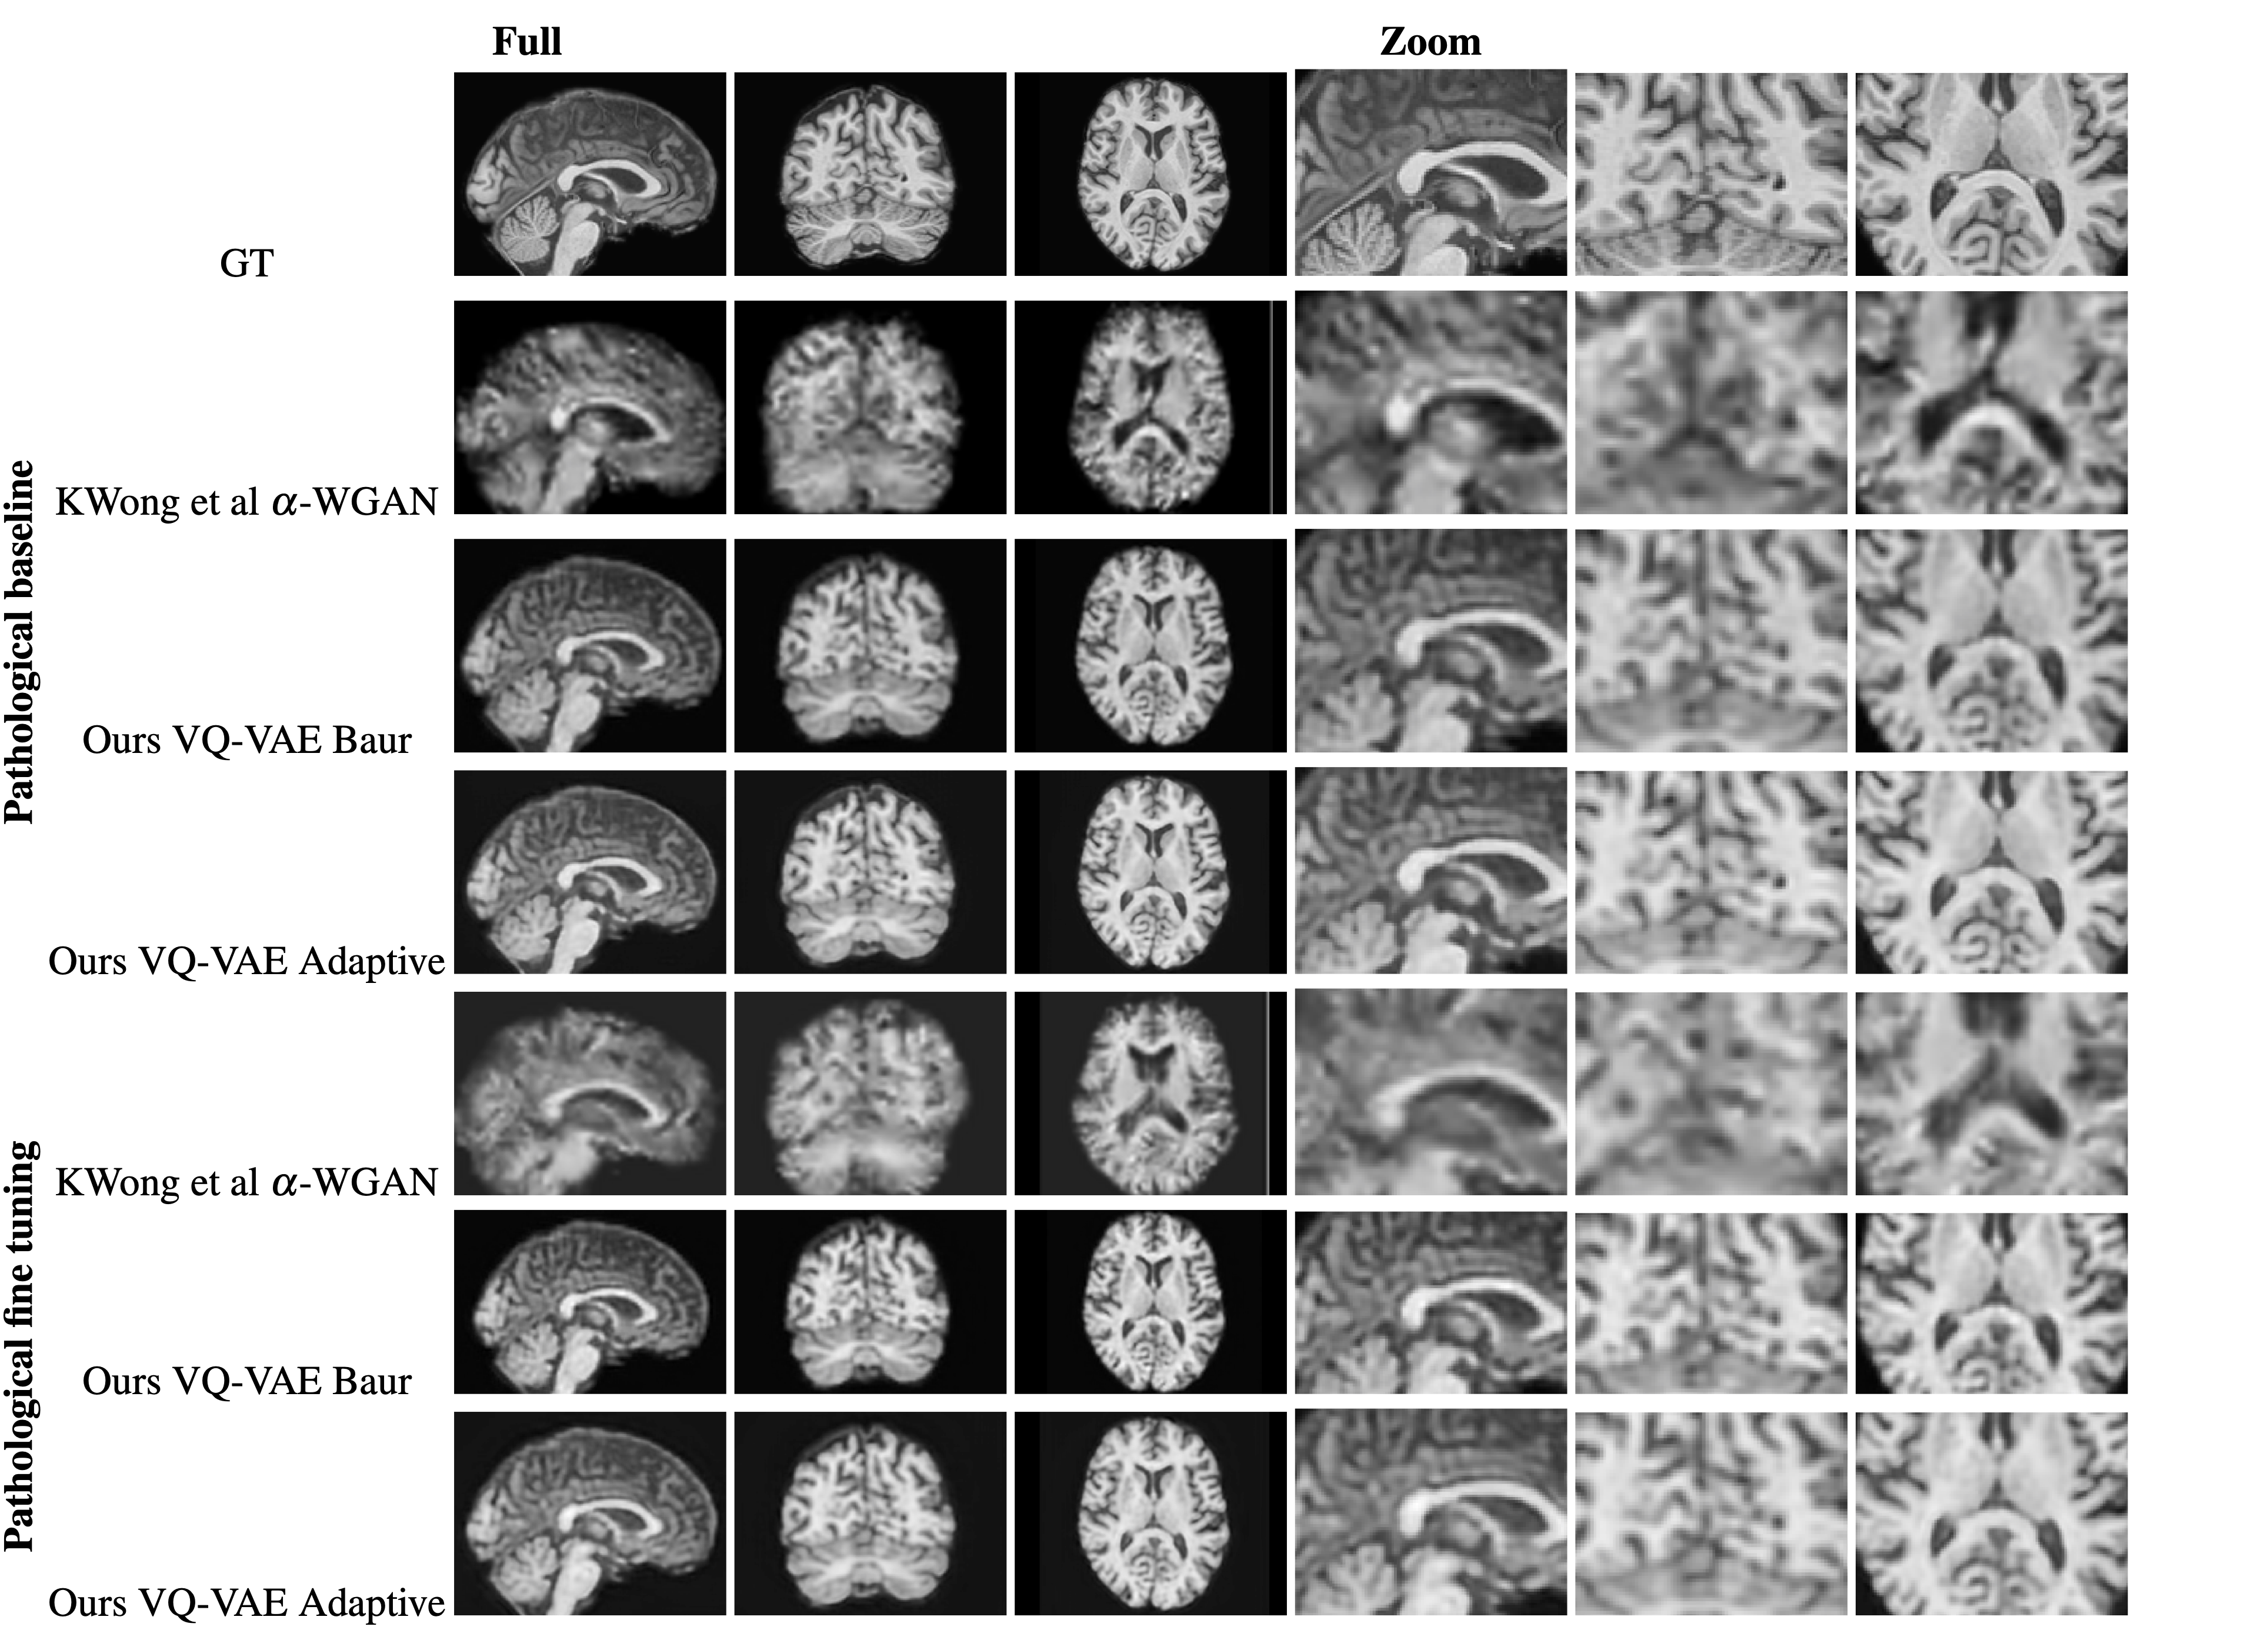

Refer to caption

Figure 5: Axial slice based representation of the an original image

Figure 6: Axial slice based representation of the reconstruction of Figure 5